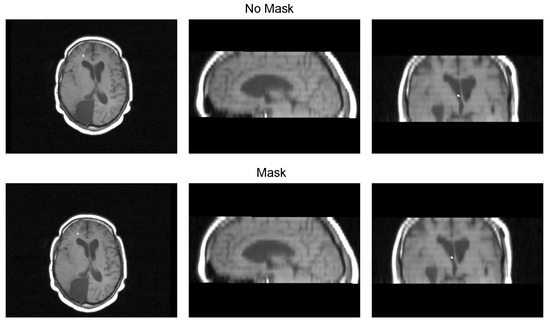

With the guidance of a medical expert, we manually localized the structures of interest, obtaining their positions in both the CT and registered MRI images using the 3D Slicer version 4.11. Upon identifying these structures, we measured the error as the Euclidean distance between the reference structure point in the CT image and the corresponding point in the registered MRI using Figure 1. For performance evaluation, we evaluated the error in images resulting from two distinct methods: (i) our proposed approach that incorporates a sampling mask during registration, and (ii) a reference method from the existing literature that conducts registration without a sampling mask. The purpose of this validation was to determine whether the use of a mask reduces registration errors. Figure 8 and Figure 9 show the methods that were compared.

Figure 8. Proposed method that uses a sampling mask for the registration.

Diagnostics 13 03420 g008

Figure 9. Method to compare that does not use a sampling mask in the registration.

Diagnostics 13 03420 g009